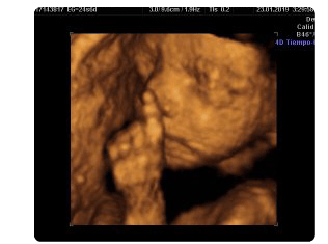

Ideeën 128 Diferencia Entre Ecografia 3D Y 4D Vers. La diferencia principal es que en el caso de la ecografía 4d, la imagen ofrecida se renueva de forma continua por lo que el efecto es el de un vídeo o película en el que se observan, además del aspecto del feto, los movimientos que este realiza. Esto hace posible que las gestantes y familiares reconozcan las imágenes que aparecen en el monitor, cosa que no pasaba con las ecografías 2d , en las que sólo el especialista lograba interpretar las imágenes. Conozca las diferéncias entre ecografía 3d, 4d y 5d.